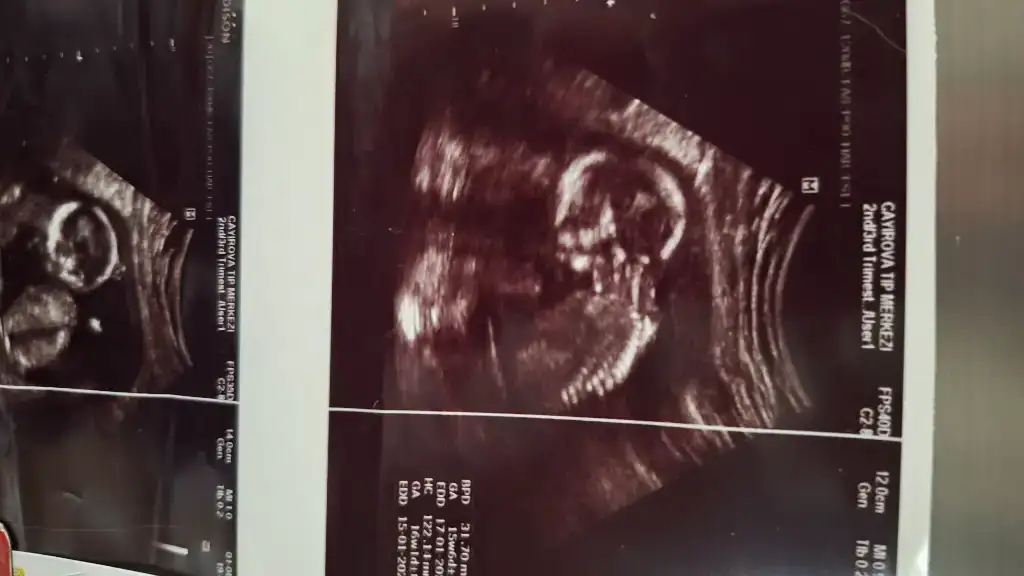

Doktorumun yuzde90 dedigi ihtimali soyledi evetÜcretsiz olan yermi doğru mu bildi yani

Devletteki doktor mu? Cihazlari eski oldugu icin yanilabiliyorlarBende anlamadım geçen haftaki yorumuyla bu haftaki yorumu çok çelişkili neden böyle olduki yanet görmüştük bacak arasını iki çizgiyi, bugünde gösterdi boş ama neden erkekte olabilir dedi buhaftadan önce erkek olduğunu öğrenip pipi görenler var

Benimde 16 hafta 2 gün göstermiyorSelam kızlar bugün kontrolüm vardı aynı zamanda ikili tarama testi için gittim 12+5 haftalık çıktı ultrasonda doktor cinsiyeti göremedim dedibaya da uğraştı sonra radyoloji uzmanı ense ölçerken ona sordum erkeğe benziyor dedi sizin varmı yorumunuz ultrason cihazı kötü biraz

Hayır özel bir hastaneye gitmiştim yani geçen haftayla aynı bunu verdi, ekranda bacak arasını gösterdi boştu kendinde söylüyor boş diye ama çıkıntı var erkekte olabilir kızda diyorDevletteki doktor mu? Cihazlari eski oldugu icin yanilabiliyorlar

Kiz genelde 3 cizgi oluyor ama artik 15 haftada netlesir yani cinsiyet